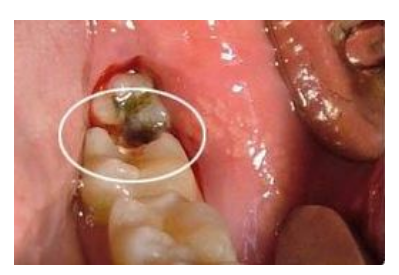

齲齒都有哪些治療方法?不痛可以不用管嗎?